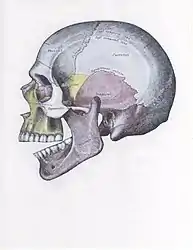

Side view of the skull with anterior dislocation of jaw.

Side view of the skull with posterior dislocation of jaw.

Side view of the skull with superior dislocation of jaw.

Front view of the skull with lateral dislocation of jaw.